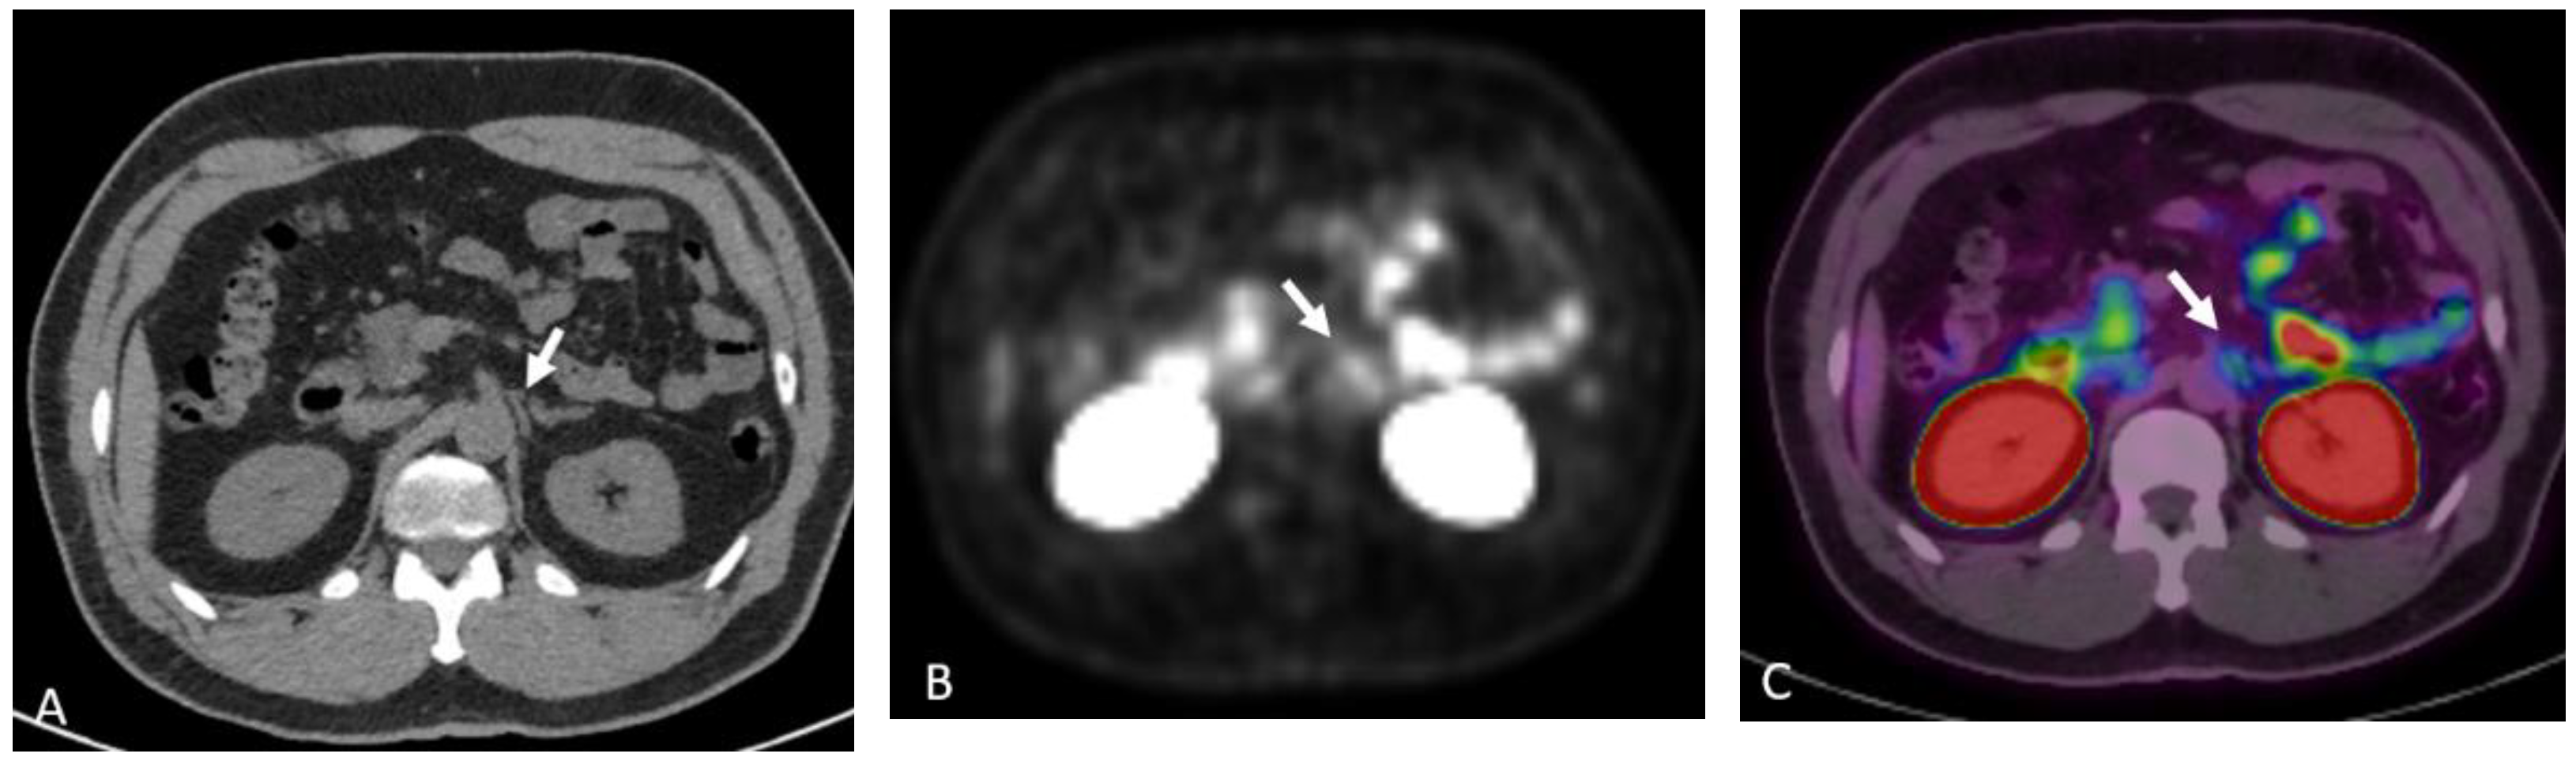

Detection of Loco-Regional Disease and Distant Metastases

Detection of Loco-Regional Disease and Distant Metastases

1.9.3. Pearls and Pitfalls